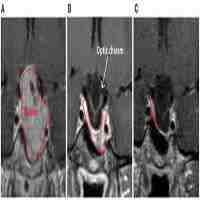

| Description | Background: The goal of this study was to relate diffusion MR measures of white matter integrity of the retinofugal visual pathway with prolactin levels in a patient with downward herniation of the optic chiasm secondary to medical treatment of a prolactinoma.Methods: A 36-year-old woman with a prolactinoma presented with progressive bilateral visual field defects 9 years after initial diagnosis and medical treatment. She was diagnosed with empty-sella syndrome and instructed to stop cabergoline. Hormone testing was conducted in tandem with routine clinical evaluations over 1 year and the patient was followed with diffusion magnetic resonance imaging (dMRI), optical coherence tomography (OCT), and automated perimetry at three time points. Five healthy controls underwent a complementary battery of clinical and neuroimaging tests at a single time point.Results: Shortly after discontinuing cabergoline, diffusion metrics in the optic tracts were within the range of values observed in healthy controls. However, following a brief period where the patient resumed cabergoline (of her own volition), there was a decrease in serum prolactin with a corresponding decrease in visual ability and increase in radial diffusivity (p < 0.001). Those measures again returned to their baseline ranges after discontinuing cabergoline a second time.Conclusions: These results demonstrate the sensitivity of dMRI to detect rapid and functionally significant microstructural changes in white matter trac... |

| Abstract | BACKGROUND. The goal of this study was to relate diffusion MR measures of white matter integrity of the retinofugal visual pathway with prolactin levels in a patient with downward herniation of the optic chiasm secondary to medical treatment of a prolactinoma. METHODS. A 36-year-old woman with a prolactinoma presented with progressive bilateral visual field defects nine years after initial diagnosis and medical treatment. She was diagnosed with empty-sella syndrome and instructed to stop cabergoline. Hormone testing was conducted in tandem with routine clinical evaluations over one year and the patient was followed with diffusion magnetic resonance imaging (dMRI), optical coherence tomography (OCT), and automated perimetry at three time points. Five healthy controls underwent a complementary battery of clinical and neuroimaging tests at a single time point. RESULTS. Shortly after discontinuing cabergoline, diffusion metrics in the optic tracts were within the range of values observed in healthy controls. However, following a brief period where the patient resumed cabergoline (of her own volition), there was a decrease in serum prolactin with a corresponding decrease in visual ability and increase in radial diffusivity (p<0.001). Those measures again returned to their baseline ranges after discontinuing cabergoline a second time. CONCLUSIONS. These results demonstrate the sensitivity of dMRI to detect rapid and functionally significant microstructural changes in white matter tracts secondary to alterations in serum prolactin levels. The inverse relations between prolactin and measures of white matter integrity and visual function are consistent with the hypothesis that prolactin can play a neuroprotective role in the injured nervous system. |